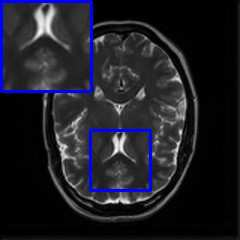

Limited by imaging systems, the reconstruction of Magnetic Resonance Imaging (MRI) images from partial measurement is essential to medical imaging research. Benefiting from the diverse and complementary information of multi-contrast MR images in different imaging modalities, multi-contrast Super-Resolution (SR) reconstruction is promising to yield SR images with higher quality. In the medical scenario, to fully visualize the lesion, radiologists are accustomed to zooming the MR images at arbitrary scales rather than using a fixed scale, as used by most MRI SR methods. In addition, existing multi-contrast MRI SR methods often require a fixed resolution for the reference image, which makes acquiring reference images difficult and imposes limitations on arbitrary scale SR tasks. To address these issues, we proposed an implicit neural representations based dual-arbitrary multi-contrast MRI super-resolution method, called Dual-ArbNet. First, we decouple the resolution of the target and reference images by a feature encoder, enabling the network to input target and reference images at arbitrary scales. Then, an implicit fusion decoder fuses the multi-contrast features and uses an Implicit Decoding Function~(IDF) to obtain the final MRI SR results. Furthermore, we introduce a curriculum learning strategy to train our network, which improves the generalization and performance of our Dual-ArbNet. Extensive experiments in two public MRI datasets demonstrate that our method outperforms state-of-the-art approaches under different scale factors and has great potential in clinical practice.